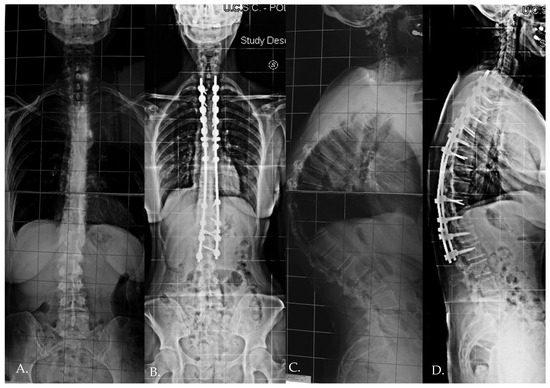

Distal junctional kyphosis (DJK) occurred in two patients, both in Group 1, where the fusion area included only the first lordotic vertebra. One patient, a 24-year-old female, was asymptomatic and maintained satisfactory correction at the 3-year follow-up. The second patient, a 23-year-old female, developed significant symptoms at the 3-year follow-up, including distal implant failure (Figure 2), which worsened her clinical condition. She experienced intractable back pain and significant sagittal and coronal imbalance. Due to hardware failure and clinical deterioration, revision surgery was required. The revision included extending the fusion to L5, interbody fusion between L1 and L2, and multiple Smith–Petersen osteotomies (Figure 3). At the 6-month follow-up, the patient showed good balance and a satisfactory reduction in pain.

Figure 2. The development of distal junctional kyphosis and implant failure reported at the 3 year follow-up (AC).